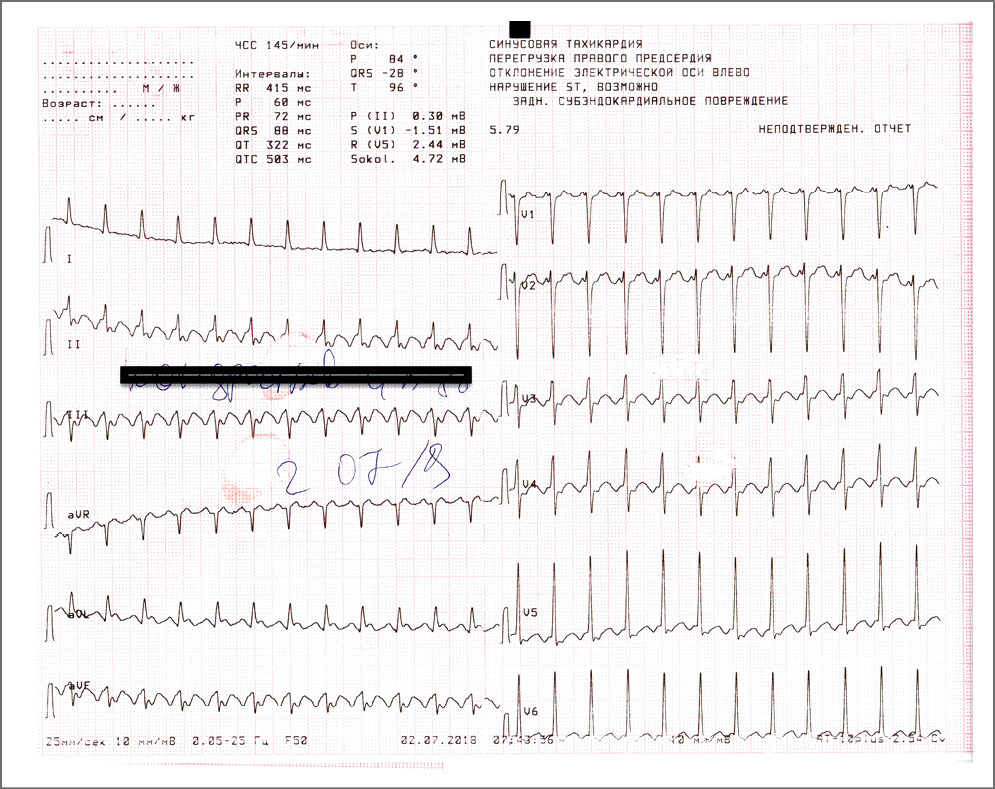

При поступлении в ГБУЗ «ГКБ №1 им. Н.И. Пирогова» состояние пациента расценено как тяжелое. Кожный покров землистого цвета, холодный на ощупь – признаки централизации кровотока. Отеки голеней, стоп. Частота дыхательных движений – 35 в минуту, инспираторная одышка. Сатурация кислорода на атмоферном воздухе 92%. Тоны сердца глухие, ритм правильный. Пульс на магистральных артериях слабого наполнения, пульс на периферических артериях нитевидный. Артериальное давление (АД) 90/40 мм рт. ст.; ЧСС 78 уд/мин. Живот мягкий, увеличен в объеме за счет асцита. Печень увеличена, выступает из-под края реберной дуга на 2 см. По мочевому катетеру мочи не получено. ЭКГ при поступлении – синусовый ритм (рис. 1).

Рис. 1. ЭКГ при поступлении в стационар: синусовый ритм